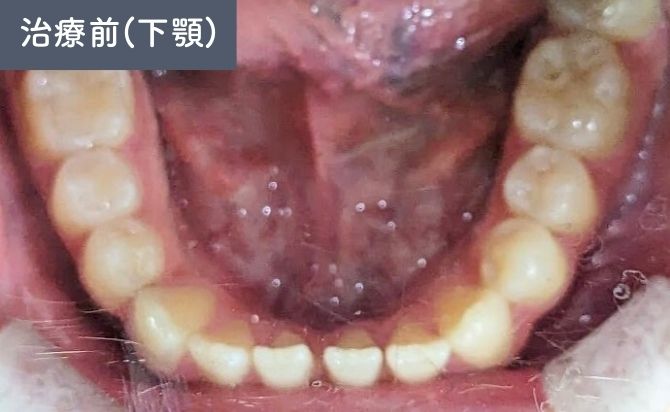

歯並びの変化(下)

診察では、上顎左右1番間の歯間空隙(すきっ歯)が認められ、審美面での改善希望が強い症例でした。また、前歯部では上下の噛み合わせが接触しない開咬(オープンバイト)の状態が確認されました。

上下前歯には軽度の前突傾向があり、歯列弓の乱れによって歯間空隙と噛み合わせの不安定さが生じている状態でした。

治療終了時には、上顎前歯の歯間空隙が閉鎖され、前歯部の開咬も改善しました。上下前歯の前突感が軽減され、歯列弓も自然な形態に整っています。

前歯部の見た目が大きく改善しただけでなく、噛み合わせも安定し、機能面・審美面の両立が図られた症例となりました。